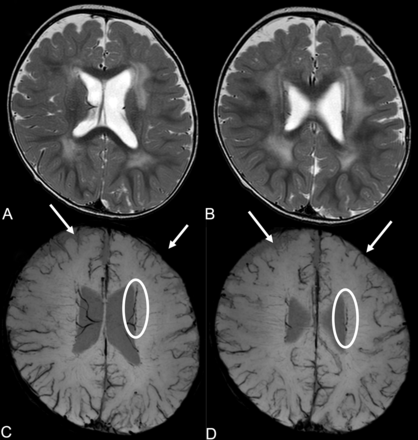

Cerebral MRIs of patient 13. T2WIs (A and B) show polymicrogyria and diffuse high signal in the white matter. SWIs (C and D) reveal hypoplasia of superficial cerebral veins in the frontal lobe (white arrows) and meandering subependymal veins (white circles).

Abnormally located superficial vessels beneath the cortex were observed in 3 patients (11.1%). The vessels ran through, inside, or beneath the lissencephalic cortex, and they were recognizable especially in the temporal lobes (Figs 1D–F and 2C–E). Hypoplasia of superficial cerebral veins around the frontal lobes was noted in all 5 patients who had SWI findings (Figs 1I and 3C, -D). Dilated and tortuous subependymal veins were identified in 2 of these 5 patients (40.0%) on SWI (Figs 1I and 3C, -D).